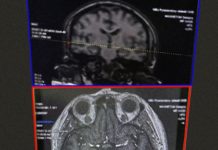

В Центре рефракционной хирургии ОКБ им. Семашко появился современный компьютерный периметр – оборудование для исследования полей зрения. Об этом сообщается в группе медучреждения в соцсети. Аппарат позволяет выявлять нарушения на ранних стадиях, в том числе при глаукоме и заболеваниях зрительного нерва.

Новое оборудование повышает точность диагностики и помогает врачам более детально оценивать состояние зрительной системы пациента.